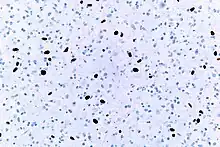

High Ki-67 expression in an invasive breast cancer, with cancer nuclei being stained (brown). There is tumor cell positivity in 70% of the cells:

High Ki-67 expression in an invasive breast cancer, with cancer nuclei being stained (brown). There is tumor cell positivity in 70% of the cells:

Ki-67 labelling index = 70% Counting positive versus negative nuclei with Ki-67 labeling, in this case in a neuroendocrine tumor of the small intestine. To count as positive, a nucleus should be at least half within the field of view, be large enough, and not be located in the stroma. Otherwise, even weakly positive nuclei count as positive.

Counting positive versus negative nuclei with Ki-67 labeling, in this case in a neuroendocrine tumor of the small intestine. To count as positive, a nucleus should be at least half within the field of view, be large enough, and not be located in the stroma. Otherwise, even weakly positive nuclei count as positive.